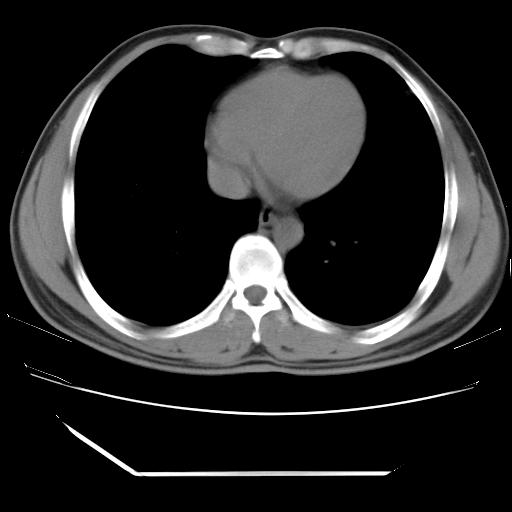

男,38岁,于2009年8月9日晚突发左侧胸痛,今x线提示左下肺阴影,为了明显确诊断,行ct检查,

血常规:嗜酸性细胞增高,单核细胞增高。

纵膈窗

病灶发生在下叶,密度均匀,边缘模糊、毛糙,周围血管纹理增强扭曲改变,靠近胸膜处病灶胸膜反应明显。

支持考虑---球形肺炎。

左肺舌叶病变。主体病灶呈类圆形中心密度低,成液化趋势周边班片影分布

考虑肺脓肿

虽然实验室检查支持炎性病变,且病变内有坏死改变(中央呈大片状低密度影),但仍不能掉以轻心,鳞癌也可以有这种影像改变。